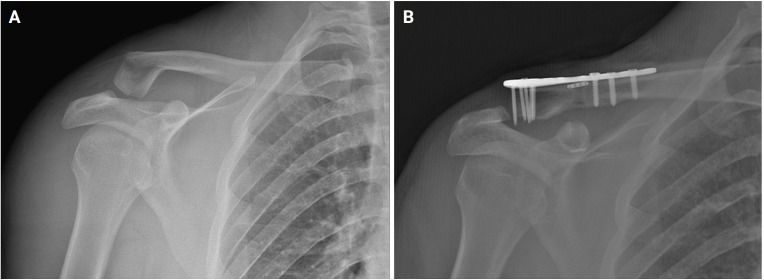

背景:喙锁韧带完整性受损的锁骨远端骨折不稳定会造成严重的不愈合风险,需要手术干预。尽管对于不稳定的锁骨远端骨折需要手术治疗的观点是一致的,但各种手术技术是可用的。本研究的目的是评估使用缝线内扣技术对2b型锁骨骨折进行CC增强的放射学和功能结果。方法:本回顾性研究将42例符合标准的患者分为两组:1组(锁定钢板加CC强化)和2组(锁定钢板不加CC强化)。记录随访期间的人口统计数据、Constant-Murley评分(CMS)、愈合时间、活动范围、并发症和种植体失败情况。结果:女性13例(31.0%),男性29例(69.0%)。平均年龄40.5±11.5岁。合并时间(周)(t(40)=-2.11, P=0.04)和6月CMS (t(40)=4.19, P=0.01)差异有统计学意义。两组术后并发症比较差异无统计学意义(P < 0.05)。结论:在2b型锁骨远端骨折的CC增强术中采用缝合内扣可获得较好的短期功能和影像学结果。证据水平:III。

Background: Instability in distal clavicle fractures with impaired integrity of the coracoclavicular (CC) ligament poses a serious risk of nonunion, necessitating surgical intervention. Despite a consensus on the need for surgery in cases of unstable distal clavicle fractures, various surgical techniques are available. The aim of this study is to evaluate the radiological and functional outcomes of CC augmentation using the suture Endobutton technique for Neer type 2b clavicle fractures were evaluated.

Methods: In this retrospective study, 42 patients who met the criteria were divided into two groups: group 1 (locking plate with CC augmentation) and group 2 (locking plate without CC augmentation). Demographic data, Constant-Murley score (CMS), union time, range of motion, complications, and implant failures during the follow-up period were recorded.